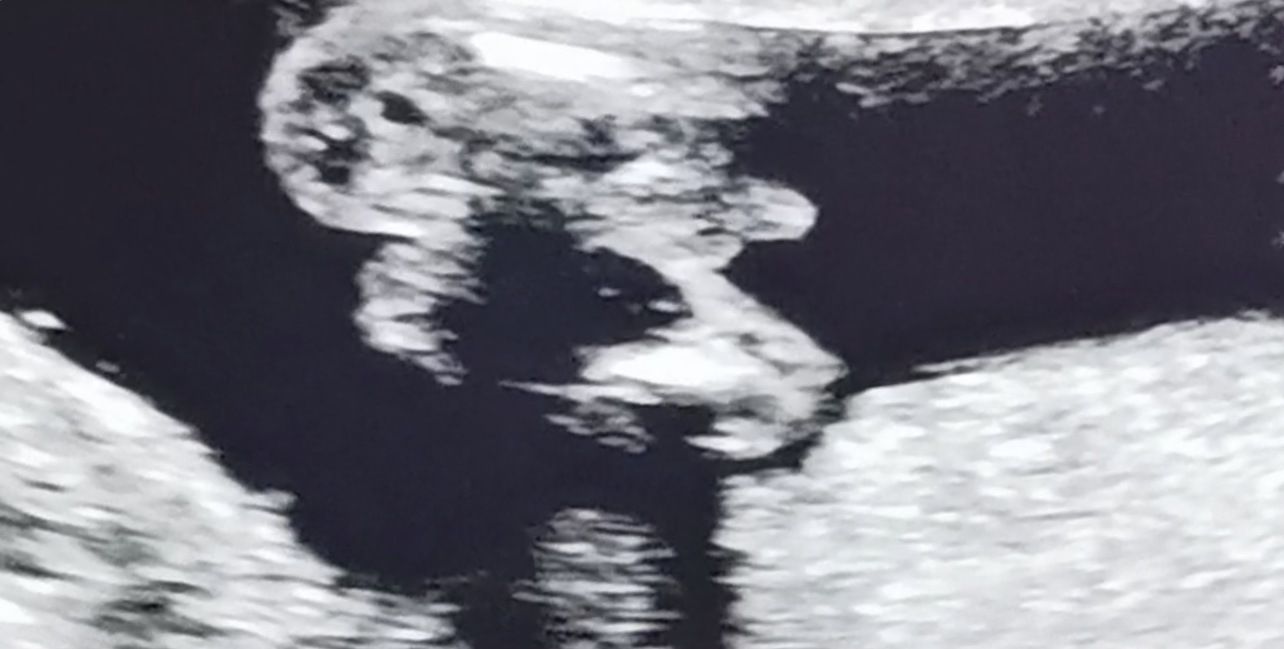

I had my anatomy scan the other day and luckily baby looks really good. We didn’t get any gender shots but I captured this from the video - is this definitely a boy?

All boy

Absolutely boy! congrats!

Boy!